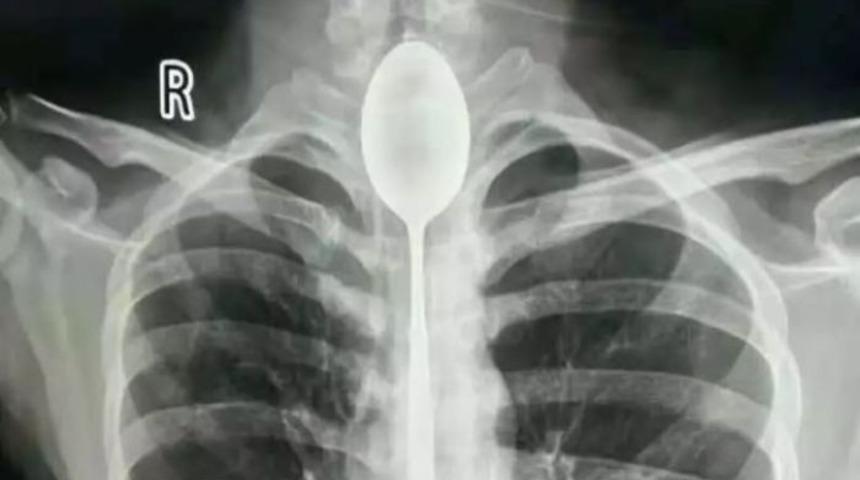

İsminin Zhang olduğunu öğrenilen şahıs, 'yapabildiğini göstermek için' 20 santimlik bir kaşığı yuttu ve uzun süre bu şekilde yaşadı. 20'li yaşlarında olan Zhang, göğsünden yumruk yiyene kadar boğazındaki kaşıkla ilgili herhangi bir problem yaşamadığını belirtti.

Çin'in ünlü sosyal medya platformlarından weixin'de yer alan açıklamada, nefes almakta güçlük çektiğini belirterek hastaneye gelen Zhang'la ilgili yapılan incelemeler sonucunda, şahsın boğazındaki kaşık tespit edildi ve acilen ameliyata alındı.

Sincan Kömür Madeni Hastanesi'nde gerçekleşen ameliyat ise oldukça zorlu geçti. İki saatten fazla süren operasyonun ardından ise Zhang'ın boğazındaki kaşık çıkarıldı.

Zhang'ın ameliyatını gerçekleştiren doktorlardan Yu Xiwu, yaptığı açıklamada "Çok şaşırdım, daha önce böyle bir olayla karşılaşmamıştım" ifadeleri kullanıldı. Hastane tarafından yapılan açıklamada, Zhang 'şanslı' olarak nitelendirildi ve metal objeleri yutmanın hayati risk taşıyabileceği vurgulandı.

Doktorlar ayrıca kaşığın mukusla kaplı olduğunu ve ciddi bir enfeksiyona neden olabileceğini söyledi.